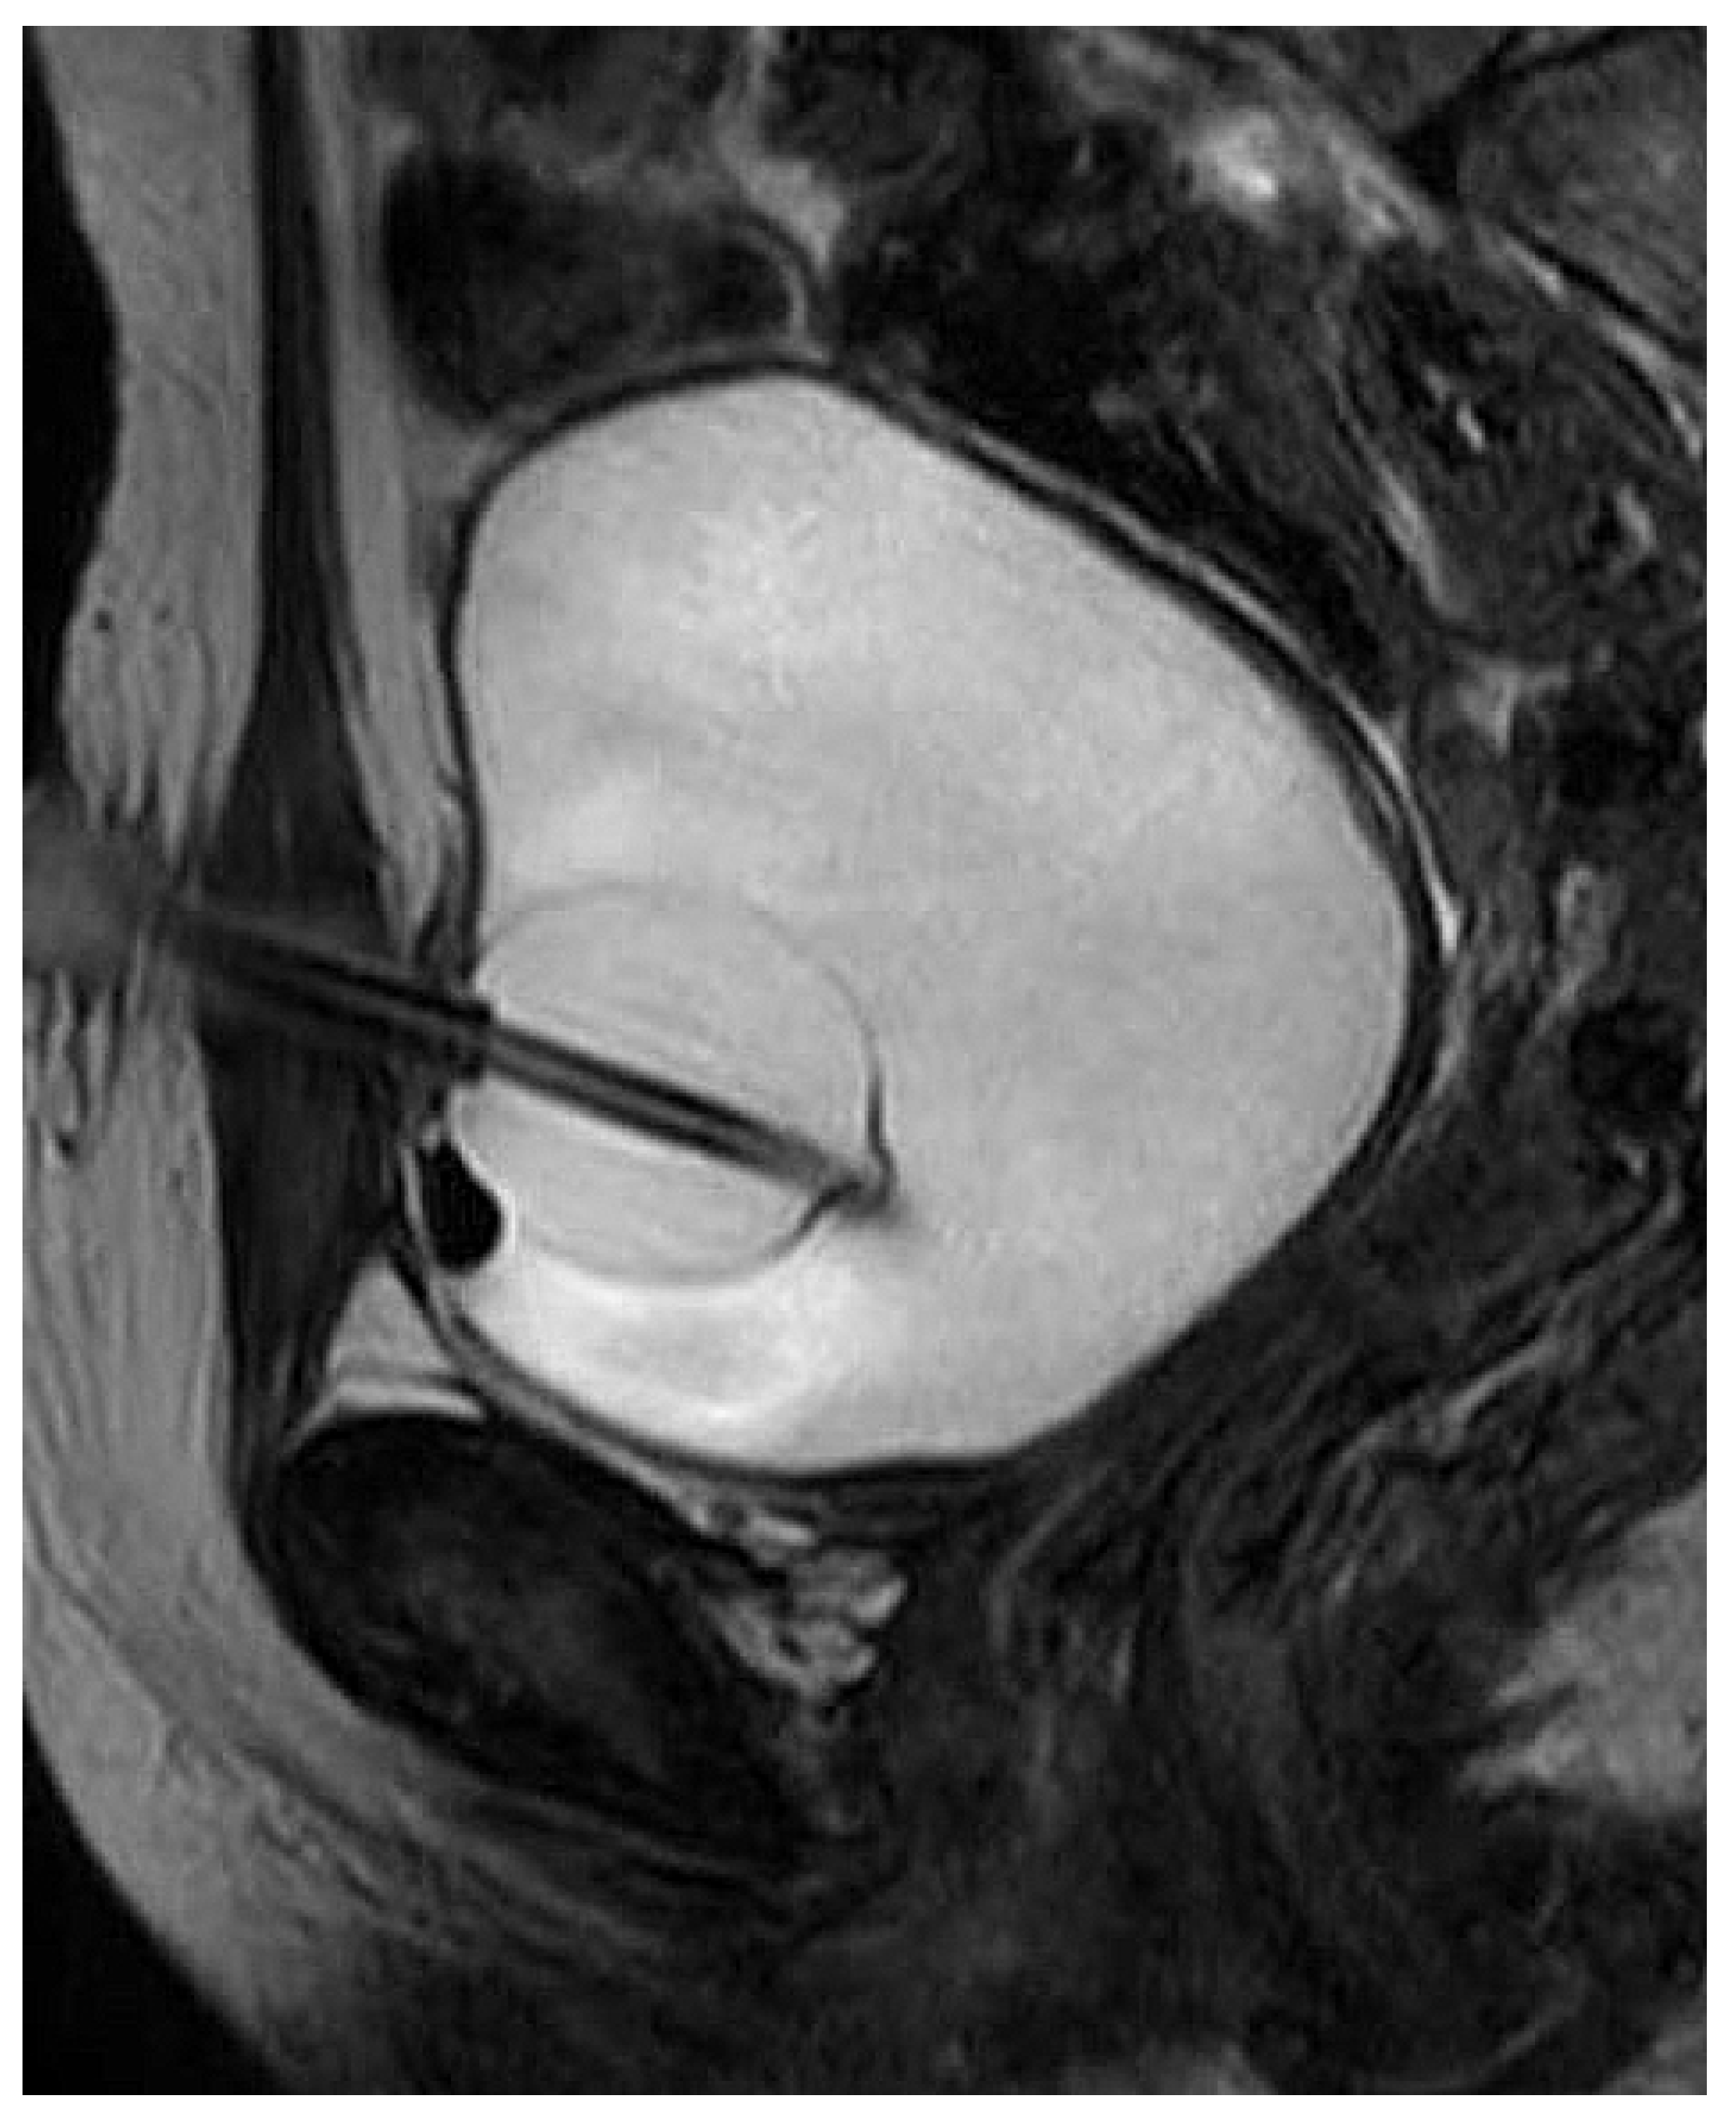

2. Materials and Methods

2.1. Approach

2.2. Transection at Bladder Neck

2.3. Transection at Proximal Urethra

2.4. Transection at Mid Urethra